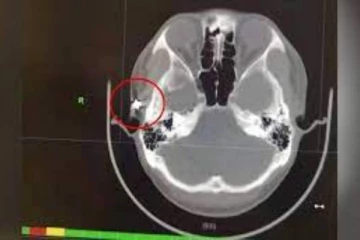

20 வருடமாக தீராத தலைவலி! ஸ்கேன் செய்து பார்த்த மருத்துவர்களுக்கு காத்திருந்த பேரதிர்ச்சி! 4 ஆண்டுகள் முன்